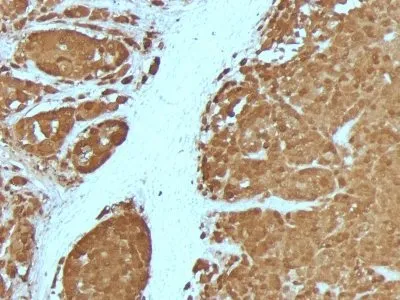

- Description: S100 belongs to the family of calcium binding proteins. S100A and S100B proteins are two members of the S100 family. S100A is composed of an alpha and a beta chain whereas S100B is composed of two beta chains. This antibody is specific against an epitope located on the beta-chain (i.e. in S-100A and S-100B) but not on the alpha-chain of S-100 (i.e. in S-100A and S100A0). This antibody can be used to localize S-100A and S-100B in various tissue sections. S-100 protein has been found in normal melanocytes, Langerhans cells, histiocytes, chondrocytes, lipocytes, skeletal and cardiac muscle, Schwann cells, epithelial and myoepithelial cells of the breast, salivary and sweat glands, as well as in glial cells. Neoplasms derived from these cells also express S-100 protein, albeit non-uniformly. A large number of well-differentiated tumors of the salivary gland, adipose and cartilaginous tissue, and Schwann cell-derived tumors express S-100 protein. Almost all malignant melanomas and cases of histiocytosis X are positive for S-100 protein._x000D__x000D_Primary antibodies are available purified, or with a selection of fluorescent CF® Dyes and other labels. CF® Dyes offer exceptional brightness and photostability. Note: Conjugates of blue fluorescent dyes like CF®405S and CF®405M are not recommended for detecting low abundance targets, because blue dyes have lower fluorescence and can give higher non-specific background than other dye colors.

- Applications: IF (verified) | IHC, FFPE (verified)

- Validated Applications: IF, IHC, FFPE

- Positive Control: Brain, Melanoma

- Additionnal Information: Higher concentration may be required for direct detection using primary antibody conjugates than for indirect detection with secondary antibody|Immunofluorescence: 1-2 ug/mL|Immunohistology formalin-fixed 0.25-0.5 ug/mL|Staining of formalin-fixed tissues requires boiling tissue sections in 10 mM citrate buffer, pH 6.0, for 10-20 min followed by cooling at RT for 20 minutes|Flow Cytometry 0.5-1 ug/million cells/0.1 mL|Western blotting 0.5-1 ug/mL|Optimal dilution for a specific application should be determined by user